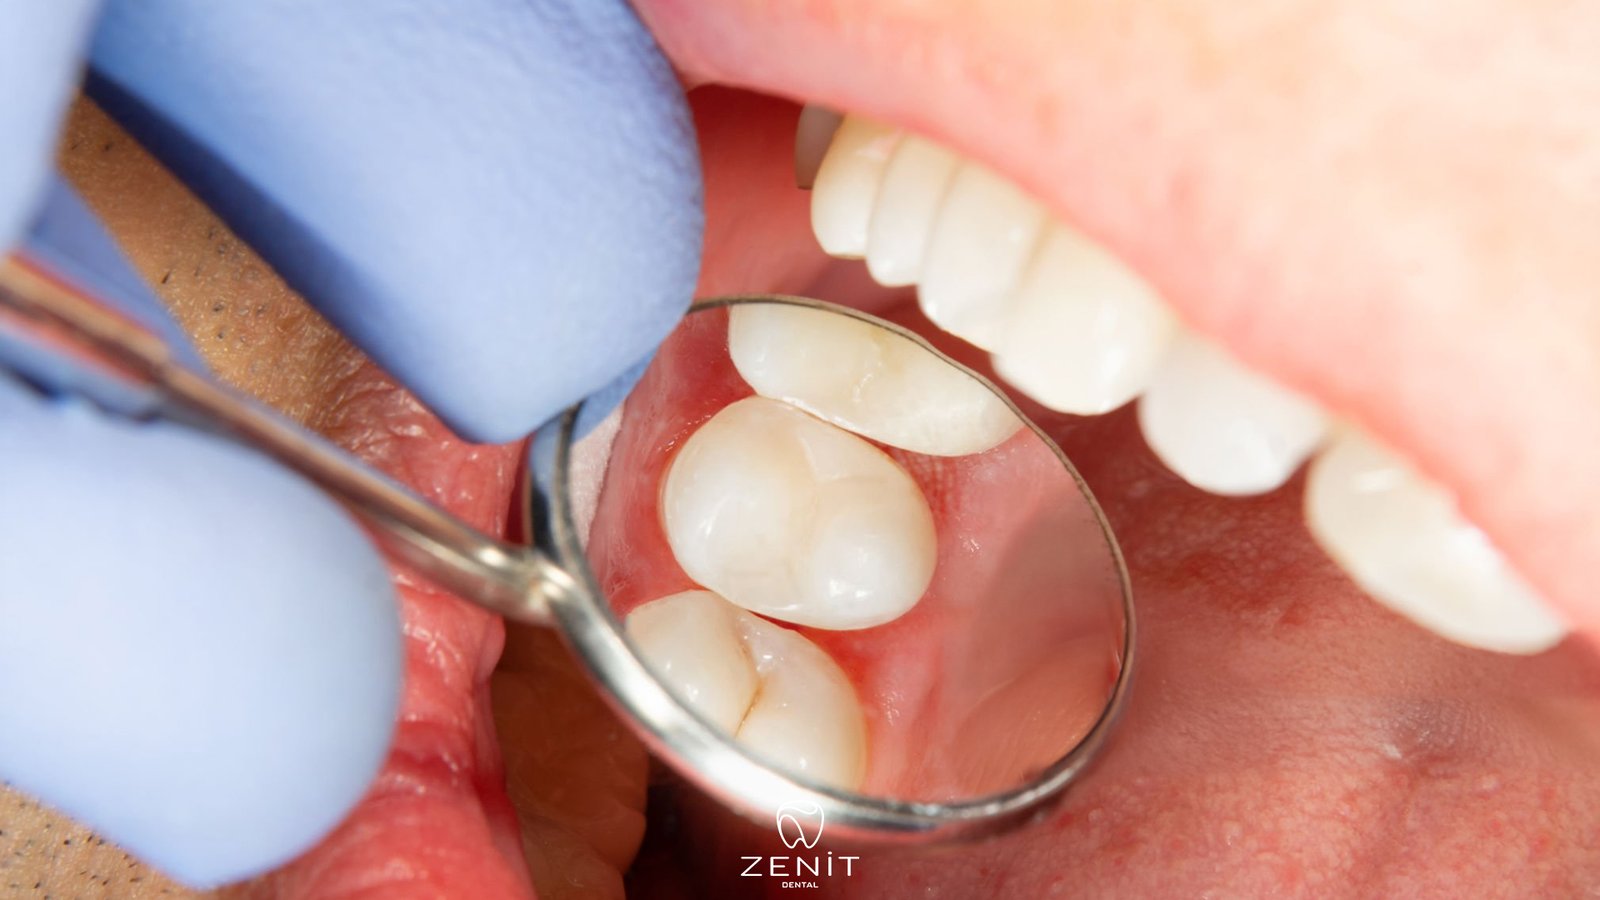

How to Protect Filled Teeth?

Protecting filled teeth is actually not as difficult as you might think; with a bit of attention and consistent habits, they can remain healthy for many years. The most basic point is not to neglect daily oral care. Brushing your teeth at least twice a day, especially before going to bed, is very important. Because at night, saliva flow decreases, allowing bacteria to multiply more easily, which can cause problems around the filling.

In addition, dental floss is something many people skip, but it is actually very effective. Food particles and plaque that remain in areas the toothbrush cannot reach can accumulate around the filling and lead to decay. Mouthwash is also a helpful addition that reduces bacterial load and provides a cleaner feeling in the mouth.

Regular dental check ups should also not be neglected. A simple check every six months allows small problems to be detected before they grow. Of course, dietary habits also matter; instead of consuming sugary foods constantly, it is much better to consume them at specific times in a balanced way.

One important detail that many people overlook is that not all fillings are the same. The material used, how well it fits the tooth, and most importantly the quality of the application directly affect the lifespan of the filling. Some fillings can last for many years without any issues, while others may start to fail earlier around the edges.

However, it is also important to remember that even the highest quality filling is not enough on its own. If oral hygiene is not maintained or dental check ups are neglected, even the best filling can eventually cause problems. In the end, daily habits are always the most important factor.